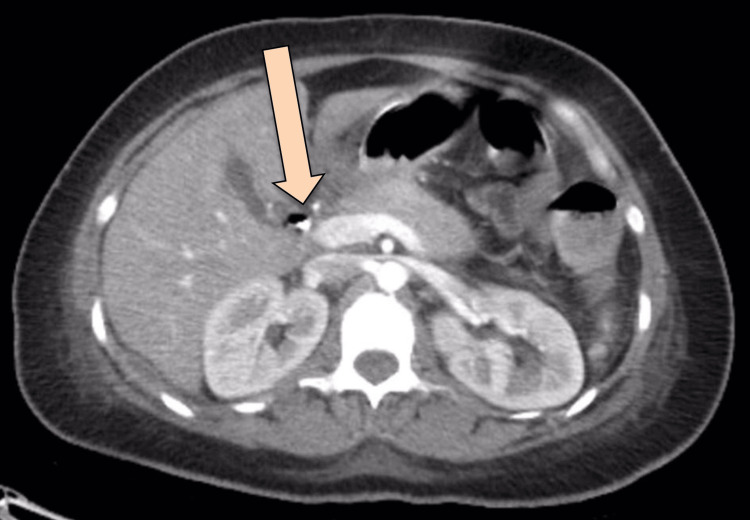

CT abdomen with IV and oral contrast post-ERCP showed pneumobilia with evidence of stent in the biliary system seen in a satisfactory position, significant pneumoretroperitoneam, small amount of retroperitoneal leaked contrast inferior to the second part of the duodenum, bulky and edematous pancreatic head, and uncinate process suggestive of acute pancreatitis, no intra-abdominal collection, and minimal amount of free fluids. There was extensive soft tissue emphysema along the anterior neck, lateral chest, and abdominal wall, severe pneumomediastinum, and minimal bilateral pneumothoraxes, with a chest tube seen on the right side in a satisfactory position, and a tiny area of contrast leakage was seen in the right posterior-lateral of the mid esophagus at T6 (Figures 2–4). The impression was double perforation at the second part of the duodenum and esophagus.

Since the patient was still tachycardic and still had leukocytosis, interventional radiology (IR) was consulted on upsizing the collection drainage to 12 French catheters. Drain output was around 100-150 ml/24 hours, billous, and started to be mixed with pus. Follow-up CT showed persistent communication of the retroperitoneal paraduodenal collection with the posterior aspect of the most distal part of the CBD. The oral contrast flow through the entire GI tract showed no evidence of a leak. Interval change in the position of the iliac fossa drain was observed, with its tip seen within the upper aspect of the right iliac fossa collection. A reduction in the size of the multi-loculated retroperitoneal collections was noted. The largest locule is seen in the right iliac fossa, which measures 9 x 4 x 12.8 cm, compared to 10 x 5 x 15 cm. Another locule was seen posterior to the duodenum, measuring 3.6 x 2.7 x 9.4 cm compared to 4.3 x 5.8 x 11 cm (Figures 6–7).